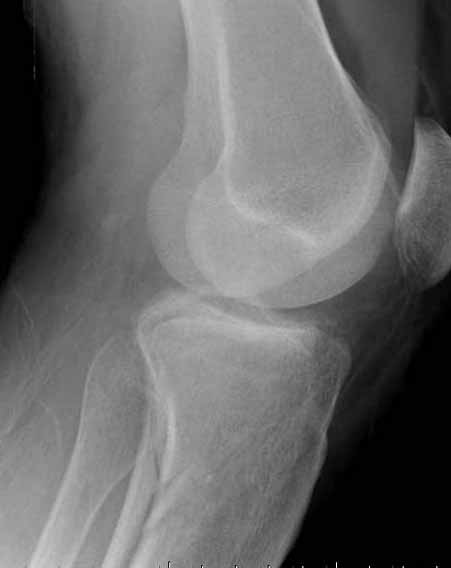

Двухколоннный перелом тибиал плато с вовлечением проксимального диафиза. Внутрисуставной компонент без смещения, и такой перелом можно лечить любым из описанных методов, о которых говорят наши коллеги.

Как понял, аппарат Илизарова не рассматривается предпочтительным для фиксации методом, хотя на фоне отека было бы идеальным для данного перелома. Для пластины требуется идеальная кожа, иначе наличие “суперсовременных имплантов” не поможет, и могут развиться серьезные осложнения.

В основном пластины рассчитаны на латеральную поверхность, потому что с латеральной стороны больше мягкотканая подушка, а также через латеральную колонну проходит ось конечности, что немаловажно в удержании оси от деформации.

Для изолированных переломов медиального тибиал плато, фиксацию можно провести “медиальной пластиной”. Некоторые компании, например Smith & Nephew делают медиальные и медиально-задние пластины, но они мягкие, и легко можно создать нужный контур. Жесткость создается за счет фиксации жесткими пластинами, например экстра артикулярной пластиной для дистального плеча от Synthes. Медиальный доступ тоже не из легких, надо работать между pes and medial gastroc.

В приложении этапы фиксации Both Column Fx и пластиной Synthes для плеча при переломе медиального мыщелка.